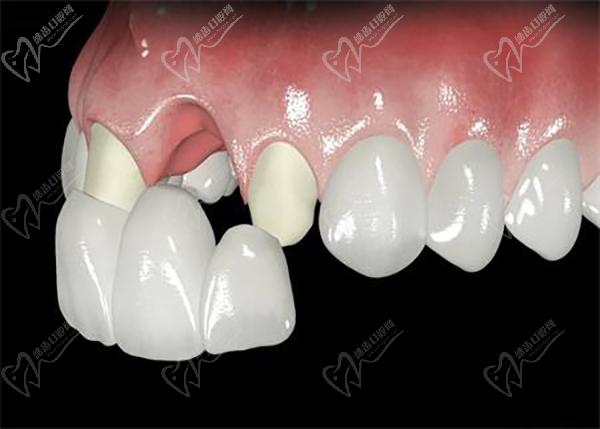

廣州柏德口腔主打德系口腔,引進(jìn)德國(guó)先 進(jìn)的口腔診療設(shè)備和技術(shù)。 注重?cái)?shù)字化技術(shù)應(yīng)用,提供更可靠的診療服務(wù)。 擁有一批經(jīng)驗(yàn)豐厚的醫(yī)生團(tuán)隊(duì),擅長(zhǎng)處理各種復(fù)雜的口腔問題。注重3D數(shù)字化種植技術(shù),術(shù)前種植牙方案模擬和設(shè)計(jì)更準(zhǔn)。也側(cè)重?cái)?shù)字化正畸技術(shù),矯正過程更精 準(zhǔn)高 效。